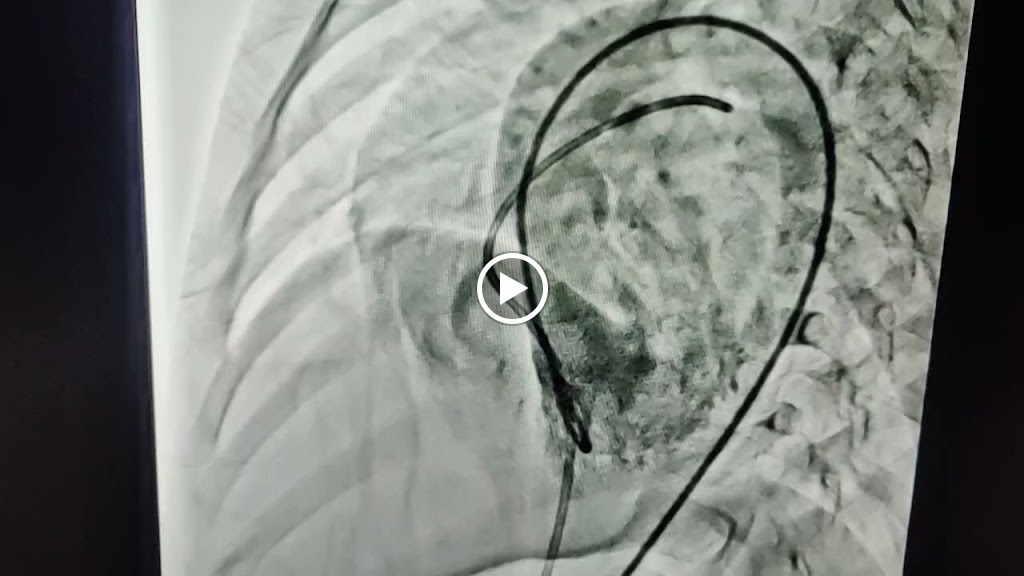

Office Gallery

Videos